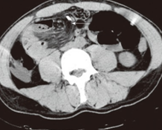

CT άνω κοιλίας με σκιαγραφικό που αναδεικνύει συστάδα διατεταμένων ελίκων λεπτού εντέρου στο κέντρο δίνοντας εικόνα κουνουπιδιού (βέλη) (Ευγενική παραχώρηση Dr. V. Penopoulos)